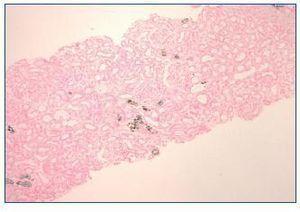

A week later, the patient reported pedal and orbital oedema and was observed on the emergency department. The physical examination was unremarkable except for hypertension (180/80 mmHg) and lower limbs oedema. Laboratory results showed haemoglobin 11.1 g/dl, serum urea 346 mg/dl, serum creatinine 9.2 mg/dl, serum sodium 130 mEq/L, serum potassium 6.5 mEq/L, serum phosphorus 6.6 mg/dl, normal serum calcium, serum bicarbonate 15 mEq/L and mild proteinuria. Serum and urine immunoelectrophoresis and immunologic study were normal. Renal ultrasound showed increased cortical echogenicity. Haemodialysis was initiated. Kidney biopsy showed minimal mesangial expansion. The tubules were mildly dilated and focal interstitial fibrosis was present. Von Kossa stain positive deposits were observed within the cytoplasm of tubular epithelial cells, tubular lumen and interstitium (figure 1 and figure 2). Immunofluorescence was negative for immunoglobulin or complement.

The second form is due to AphN with a more insidious onset (days to months) and is generally irreversible1. At the time of diagnosis, serum phosphorus and calcium levels are normal, unless measured within 3 days of bowel preparation. This was in fact the case of the first patient. As we found, the main pathologic finding in kidney biopsy is nephrocalcinosis demonstrated with the Von Kossa stain1.

Figure 1. Kidney biopsy. Von Kossa coloration (40x).

Figure 2. Kidney biopsy. Von Kossa coloration (100x).